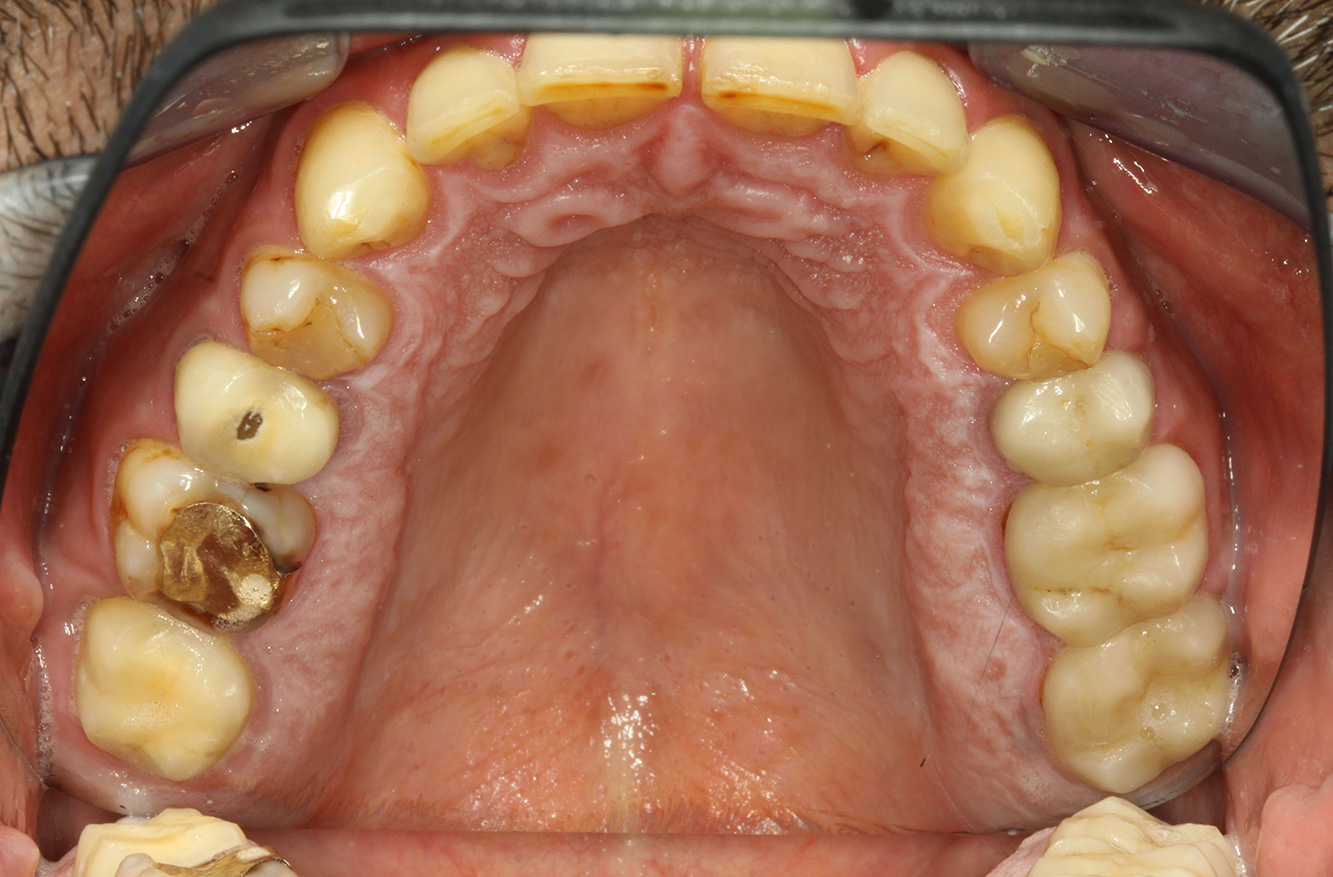

Der Patient ist 39 Jahre mit Z.n. Herzklappenersatz wegen Klappenfehlers und Endokarditis. Als Antikoagulans (Gerinnungshemmer) wird regelmäßig ASS 100 eingenommen. Aus dem Bereich Lebensstil ist die Ernährungsweise als kariesfördernd einzustufen, da mit hoher Regelmäßigkeit zuckerhaltige Lebensmittel sowie sechs bis sieben Mahlzeiten täglich verzehrt werden. Die Mundgesundheit des Patienten zeigt ein mittleres Kariesrisiko mit aktiven Läsionen. Das Parodontitisrisiko ist niedrig, es besteht eine Gingivitis. Es ergeben sich folgende Empfehlungen für die Prophylaxebehandlung.

Für die Prophylaxesitzung lassen sich keine spezifischen Instrumentierungsempfehlungen ableiten. Durch den gezielten Einsatz von Pulverstrahl und rotierend Polieren können Plaque und Verfärbungen an den Restaurationsrändern schonend entfernt und Wiederbesiedlungsnischen für kariogene Bakterien reduziert werden (20).

Zur weiteren Unterstützung der Kariesprävention ist eine Fluoridierung, besonders um der Neuentstehung im Bereich der Restaurationsränder vorzubeugen, und eine Versiegelung der Wurzeloberflächen empfehlenswert. Beide Maßnahmen können die angegebene Temperatursensibilität der Zähne reduzieren.